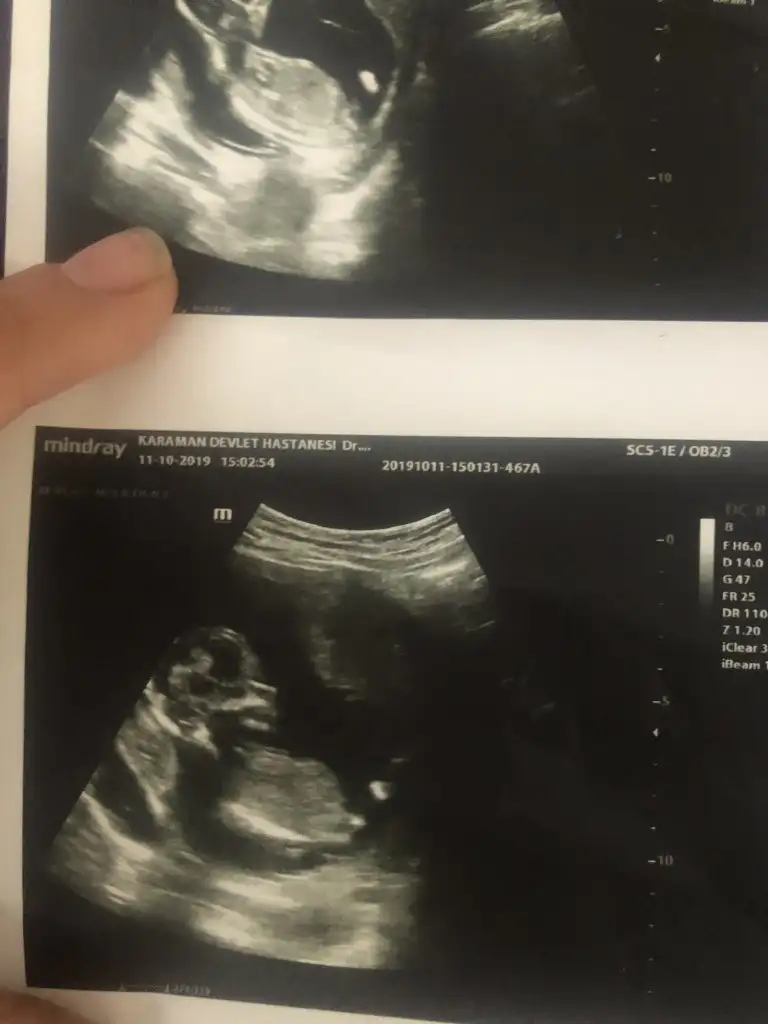

11 yada 12Kaç haftalık ultrason görüntüsü gerekli anlayabilmek için acaba ?

Hımm 9 haftalik benim bebegim olmuyor sanırım.11 yada 12

Erkek gibi ama 11 yada 12 hafta usg olmalıKızlar tahmini olan var mıı